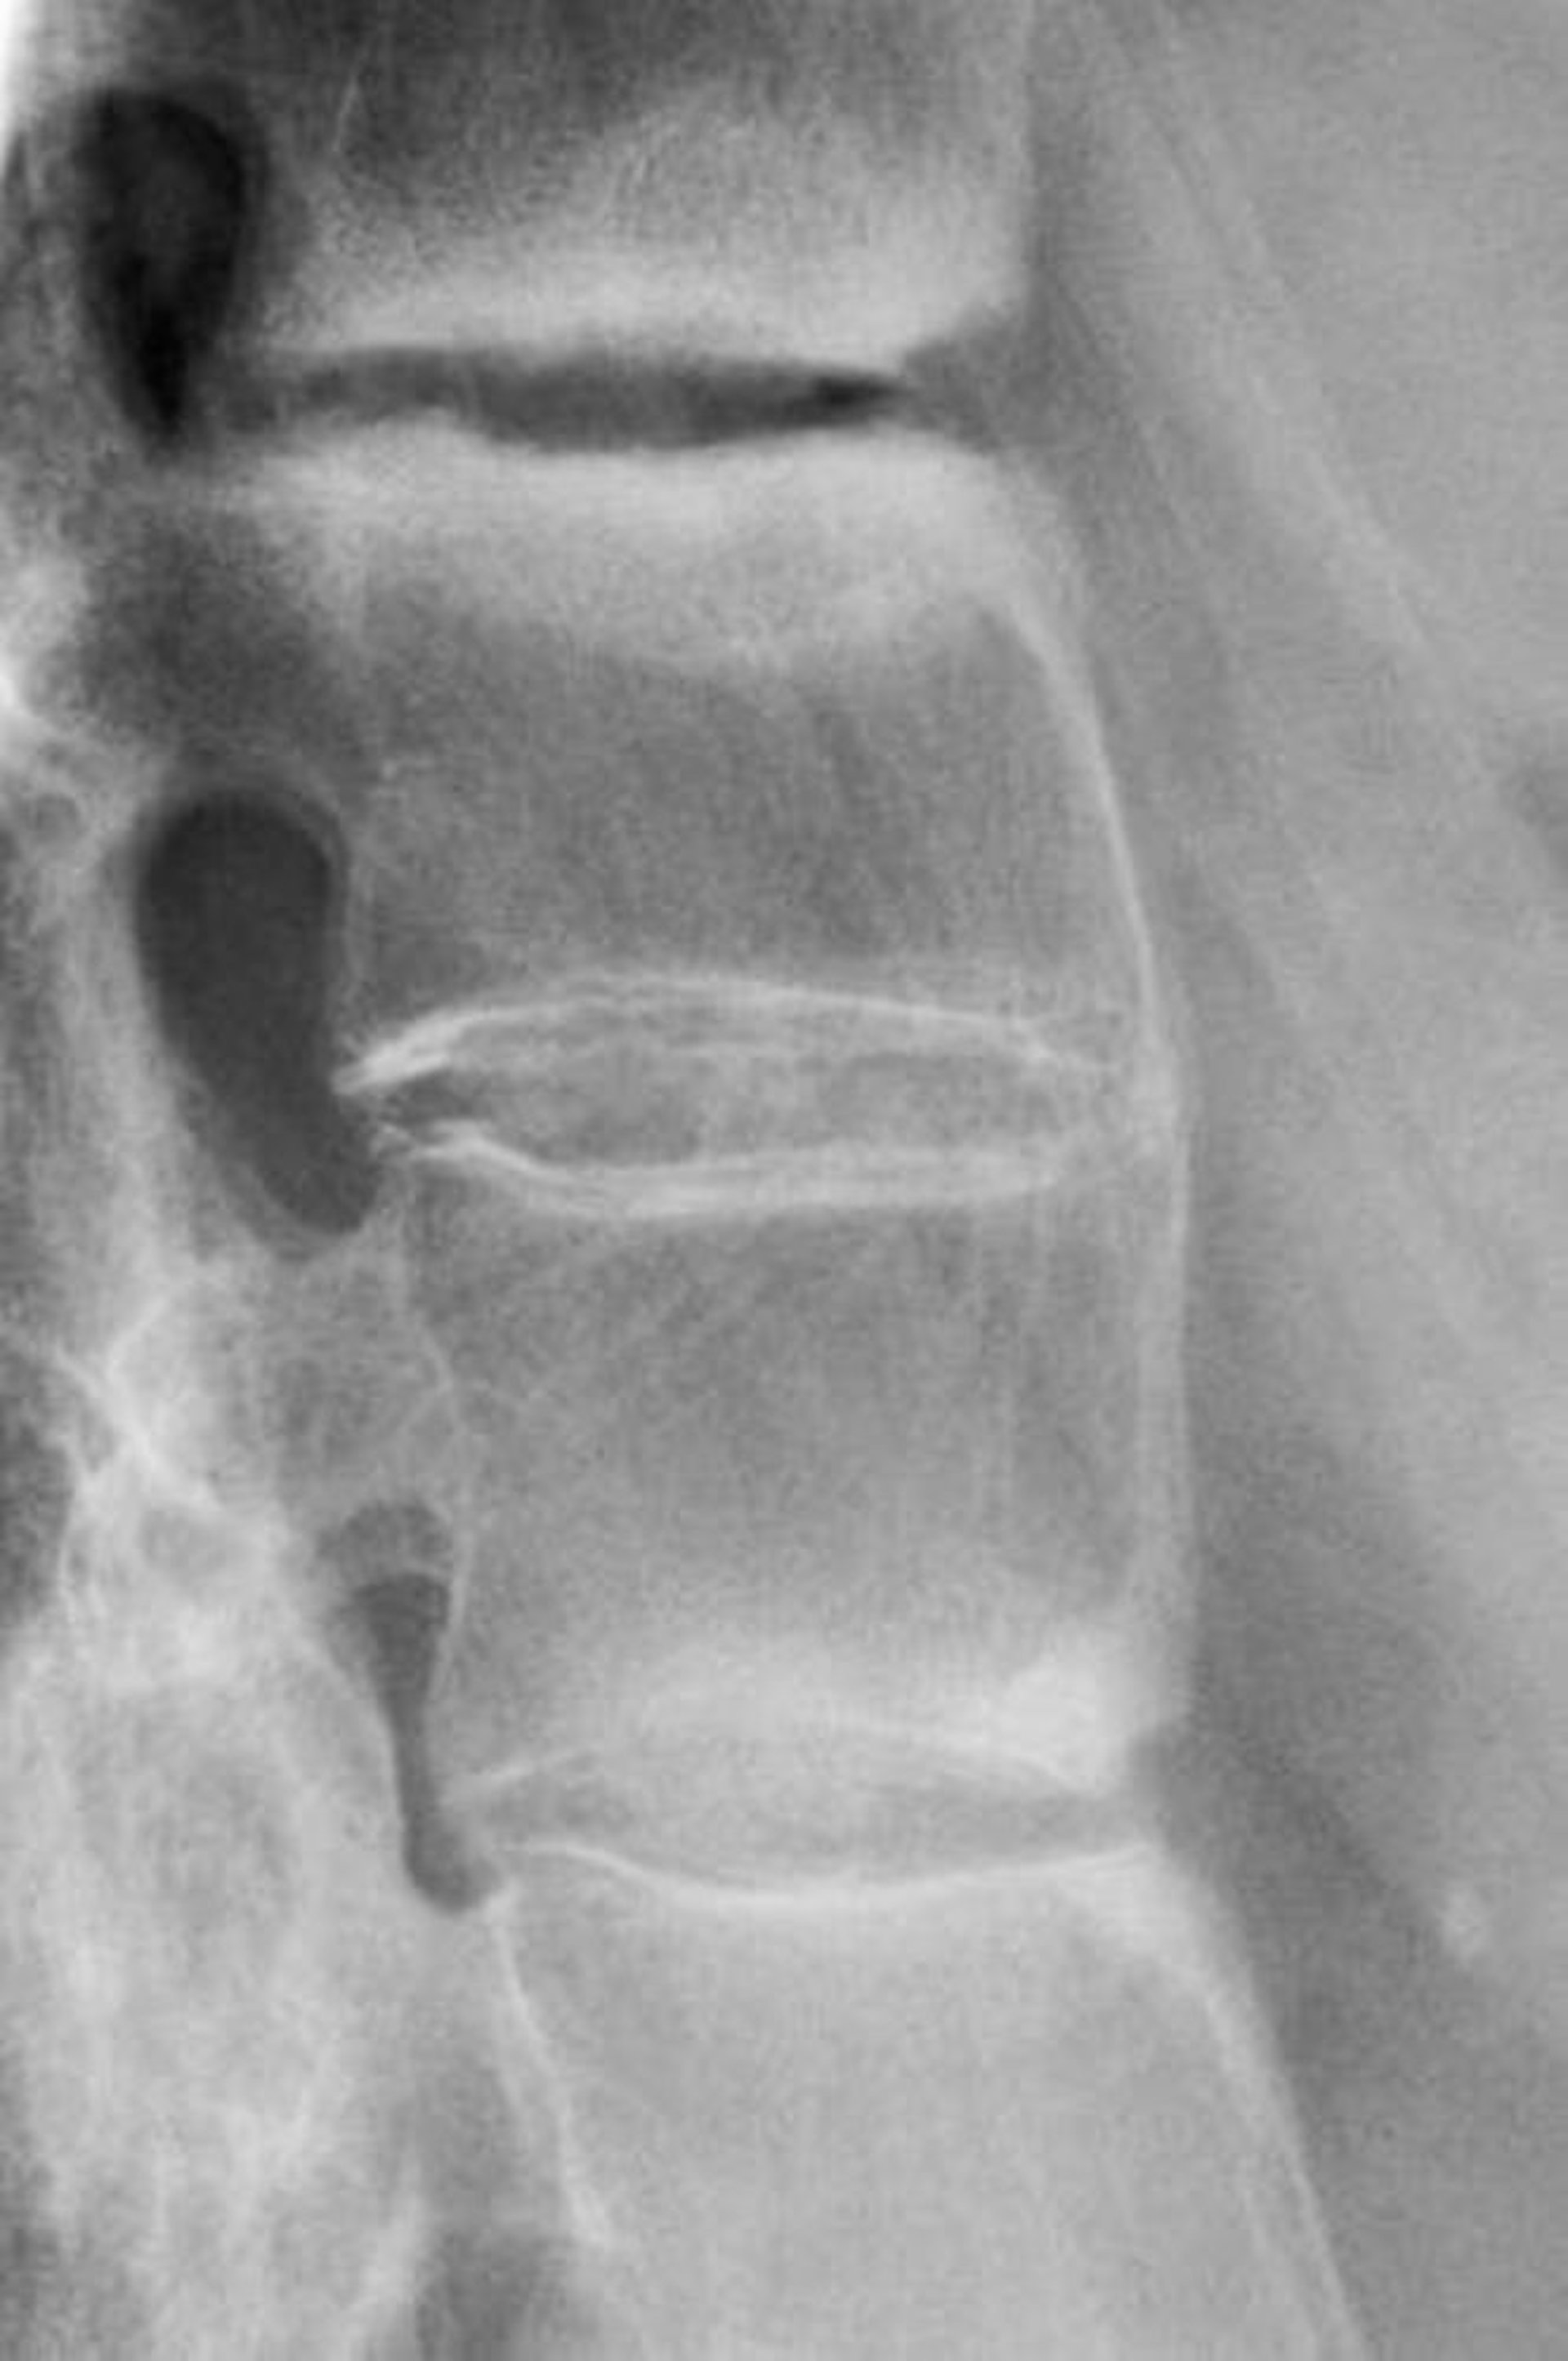

X線上の最初の異常は,軟骨下のびらんによって生じる仙腸関節の偽の開大であり,硬化または後の狭小化および最終的な癒合が続く。変化は対称性である。脊椎の初期変化は,上位腰椎の角部分の硬化に伴う方形化;斑状の靱帯石灰化(shiny corner sign);および1カ所または2カ所の進行性の靱帯骨棘形成である。後期の変化により「竹様脊柱(bamboo spine)」の外観が呈するが,これは顕著な靱帯骨棘形成,広範な脊椎周囲の靱帯石灰化,および骨粗鬆症に起因する;これらの変化は,一部の患者で平均で10年間かけて発生する。

この強直性脊椎炎患者の脊椎X線写真では,椎骨間に余分な骨(明るい白色)が認められる。癒合が完全な部位では「竹様脊柱(bamboo spine)」の外観を呈する。

ZEPHYR/SCIENCE PHOTO LIBRARY